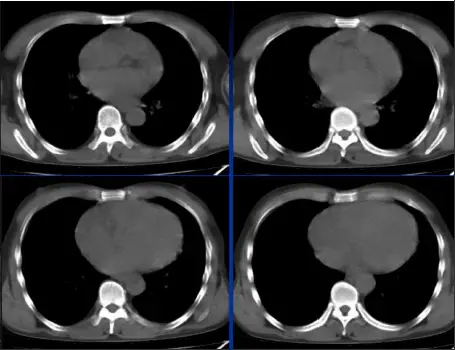

病例:男,28岁,溺水肺水肿,溺水1小时,咳嗽,呼吸困难,咳粉红色泡沫样痰,肺部听诊大量湿啰音。

CT表现

肺泡性肺水肿:两肺透光度减低,并见广泛性分布结节样、斑片样密度增高影及毛玻璃样影,以两肺内、中带分布较明显,右侧较左侧多。

溺水性肺水肿,以肺泡性为主,右肺明显,结合病史即可明确诊断。